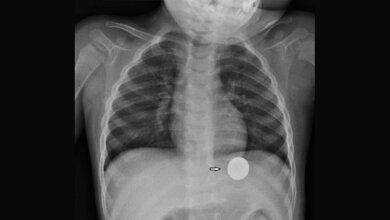

Anomalien und Normvarianten: noch einmal anders – alltägliche und nicht alltägliche Artefakte (Teil III)

Die Magnetfelder der MR-Tomografen können zu Interferenzen mit ferromagnetischem Material und gefährlichen Interaktionen führen. MR-Abteilungen sollten das Vorhandensein von metall- oder mineralhaltiger Kosmetik oder Haarprodukten ins Screening-Protokoll der Vorbereitung der Untersuchung aufnehmen. Neue Techniken können zur Artefaktreduktion führen. Algorithmen zur Artefaktsuppression stehen zur Verfügung.

Schlüsselwörter: Artefakte, Röntgen, Ultraschall, CT, MRT

Magnetic fields can interfere with ferromagnetic material leading to many dangerous interactions. MRI centers should include the use of metal- or mineral-based facial cosmetics or hair products in the screening protocols. Newer techniques are available to further reduce artifacts. Algorithms for metal artifact suppression are also available.